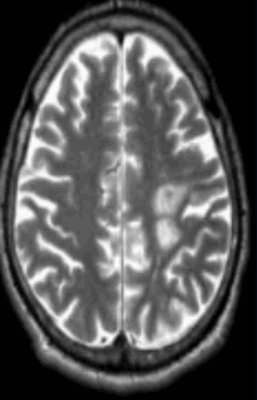

Классический пример МРТ снимков головного мозга показан на рисунках ниже. Магнитно-резонансная томография выполняется в поперечной (или аксиальной - рисунок снизу) и продольной (или сагиттальной — рисунок сверху) плоскостях.

Исследование выполняется в нескольких режимах. Основные из них Т1 и Т2. Изображения, полученные в данных режимах, часто также называют Т1-взвешенными или Т2-взвешенными снимками. Изображения, показанные выше, сделаны в Т1-режиме.

Главное отличие этих режимов - в том, как на снимках отображается жидкость и воздух. В Т1 режиме ткани, содержащие большое количество воды, имеют более темную окраску, в то время как в Т2 режиме они яркие, светлые. Это легко понять, посмотрев на снимки выше - глазные яблоки визуализируются в виде светлых парных округлых образований с одной стороны яркие и светлые, с другой - темные. Следовательно, снимок справа сделан в Т1 режиме, снимок слева - в Т2. Также существует разница в том, как в этих режимах отображается серое вещество головного мозга. В Т2 режиме оно светлее, чем белое вещество.

Как же узнать, есть ли на снимках признаки болезни? Самое главное - запомнить, как выглядит головной мозг здорового человека. Врач, изучая снимки пациентов, постоянно сравнивает их с нормальными снимками, хранящимися у него в голове. Чтобы понять, как это происходит - посмотрите на снимки внизу:

Перед вами - два снимка, сделанных в одном режиме. Снимок снизу - норма. Какое заболевание, в таком случае, есть на верхнем снимке? Чтобы понять это, нужно сравнить эти изображения. Явно видно отличие - на верхнем снимке в правой части головного мозга есть новообразование. Разница еще заметнее, если сравнить левую и правую части того же снимка.

Отметим его красной окружностью. Визуально оно представляет собой узел, неоднородный по окраске и отличающийся от серого и белого вещества головного мозга. В таких случаях, чтобы точно определить границы опухоли и определить её тип исследование повторяют с контрастом. Введение контрастного препарата в кровь через локтевую вену приводит к накоплению контрастного вещества в тканях опухоли - нормальные здоровые ткани его практически не накапливают. И мы получаем следующую картину, показанную на рисунке справа. Яркая окраска опухоли соответствует накопленному контрасту - теперь можно не только сказать, где опухоль, но и примерно определить, что это доброкачественная опухоль, так как она имеет четкие границы (злокачественные опухоли прорастают окружающие ткани, из-за чего границы будут размытыми и не такими четкими).

Таким образом расшифровка результатов МРТ головного мозга проводится путем сравнения полученных снимков с нормой. При отсутствии отличий можно говорить о том, что пациент, чьи снимки исследует врач, скорее всего здоров. Сравнивается все - форма, размеры анатомических структур, локализация, симметричность, количество спинномозговой жидкости в полостях головного мозга, и множество других параметров. Каждое заболевание, будь то инсульт или рассеянный склероз, имеет свои характерные признаки.